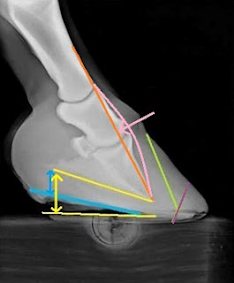

El grado de separación entre la banda de la corona y el proceso extensor (líneas naranjas) demuestra una cantidad moderada de descenso distal. Es probable que el apoyo disminuido por la cápsula del casco desequilibrada en relación con el hueso fuera suficiente para permitir que la columna ósea descendiera.

Evaluación

lateral. El tercio superior de la pared está alineado con la posición actual

del hueso de la 3er. falangue. Hay un “punto de cambio de ángulo” en la pared

del pie (flecha negra), clásico con antecedentes de hundimiento.

Un aspecto fundamental del ajuste de realineación es hacer retroceder el dedo del pie para que esté alineado con la posición actual del hueso de la 3er. falangyue (línea morada). Esto reduce el apalancamiento sobre la lámina durante la rotura al permitir que el hueso se rompa correctamente.

La rotación

ósea se demuestra cuando los huesos se han salido de la relación correcta con

el suelo y entre sí. La rotación capsular implica que la cápsula del casco está

desequilibrada con la columna ósea (línea naranja/eje 1er. Falangue-3er.

Falangue). Un casco puede tener uno, ninguno o ambos.

El casco en

la Foto demuestra tanto la rotación ósea como la capsular. En un pie sano, el

ángulo palmar, o la parte posterior del hueso de la 3er. Falangue (flecha

amarilla), generalmente se encuentra a unos 5 grados (+/-) del suelo. La

columna ósea está alineada (naranja), sin que se incline hacia adelante (rosa)

ni hacia atrás. Al bajar los talones a la línea azul, otro aspecto fundamental

de un ajuste de realineación con rotación ósea, los huesos se

"desrotarán" (flecha rosa) y el ángulo de la palma volverá a unos 5

grados (flecha azul). Por lo general, sucede tan rápido como eso.

La rotación capsular se puede abordar retrocediendo el dedo del pie para librar el pie del ensanchamiento del dedo del pie (línea morada).